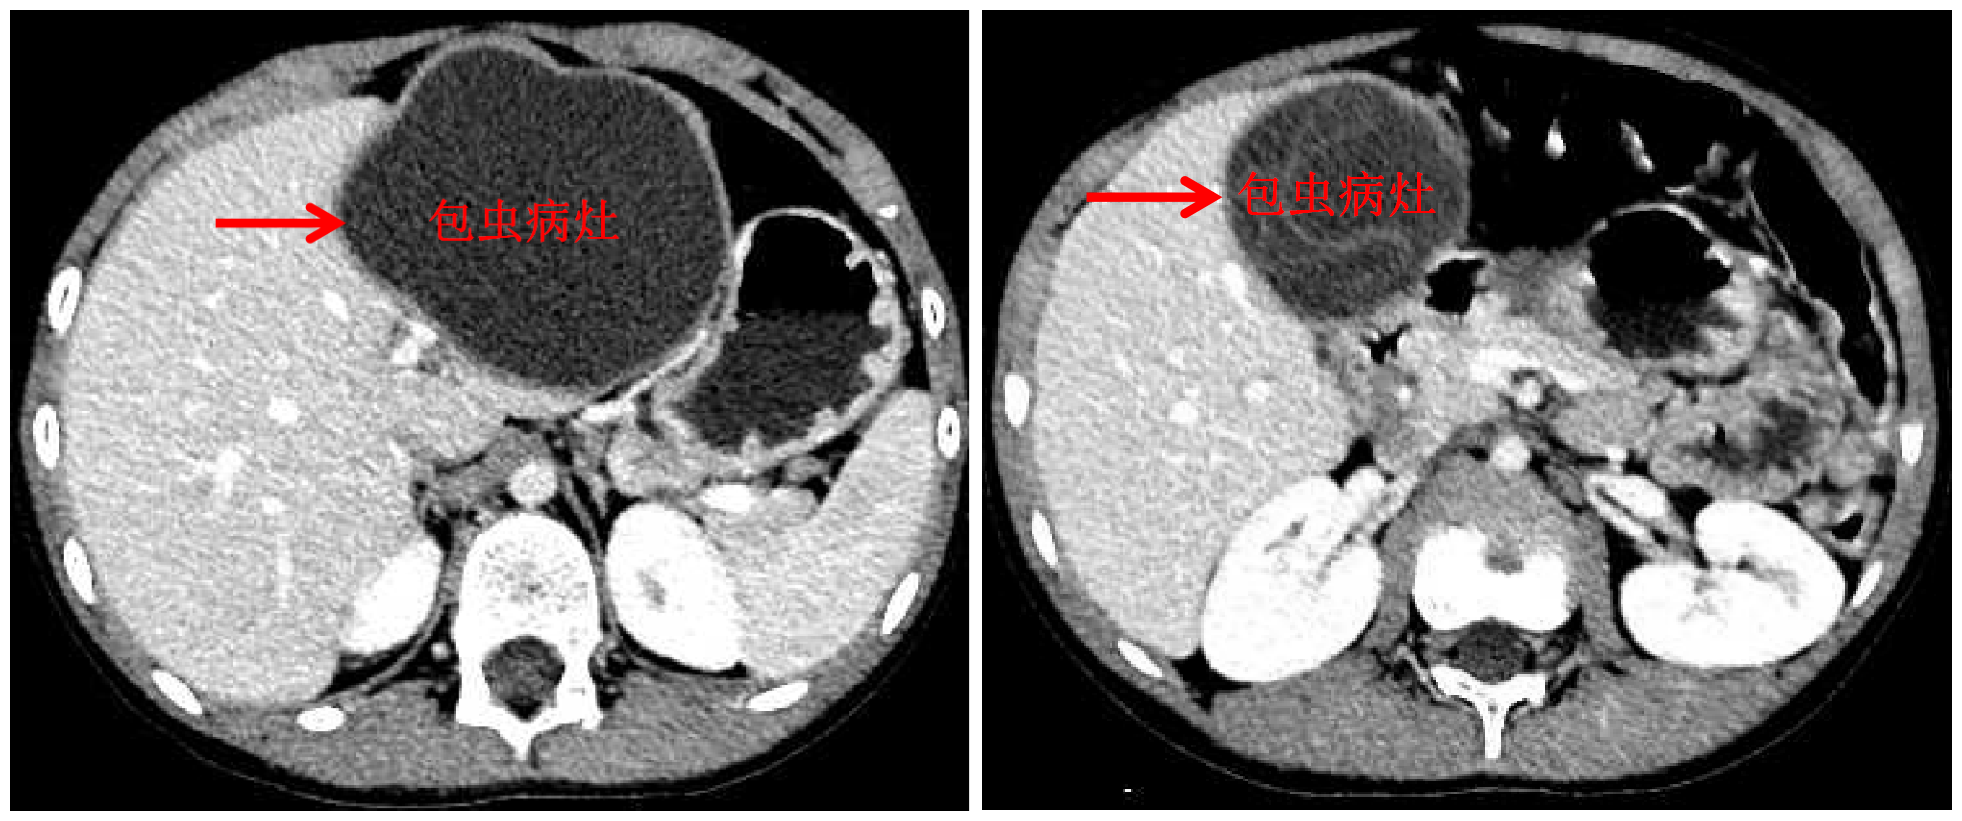

AG(中国)AG·官方网页版网10月13日电 国庆前,8岁的小扎西被父亲带到了西藏大学附属拉萨市人民医院普外科,此次距离孩子确诊肝包虫病已有一年之久。腹部影像显示,小扎西体内的囊型肝包虫病已经侵袭了左肝大部。

包虫病灶